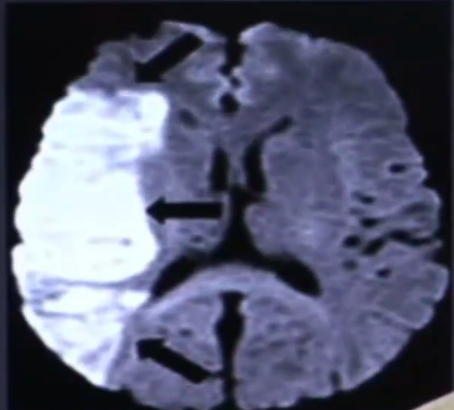

Qual o exame padrão ouro para detectar isquemia cerebral ?

Sequência de difusão na RNM (edema intracelular por conta da perda da bomba de Na e K)

O que é penumbra?

A diferença entre uma área de perfusão e uma área de difusão

O que é um AVC lacunar?

É um AVC de uma artéria terminal (perfurante) < 2 cm de diâmetro